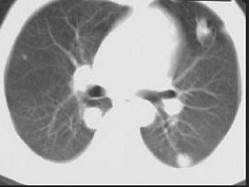

问题 男,40岁,化脓性胆管炎手术后三天出现高热,伴胸痛,咳嗽,CT如图,最可能的诊断为 ( )

选项 A、肺多发性脓肿 B、肺组织胞浆菌病 C、金葡菌肺炎 D、肺淋巴瘤 E、肺转移癌

答案 A